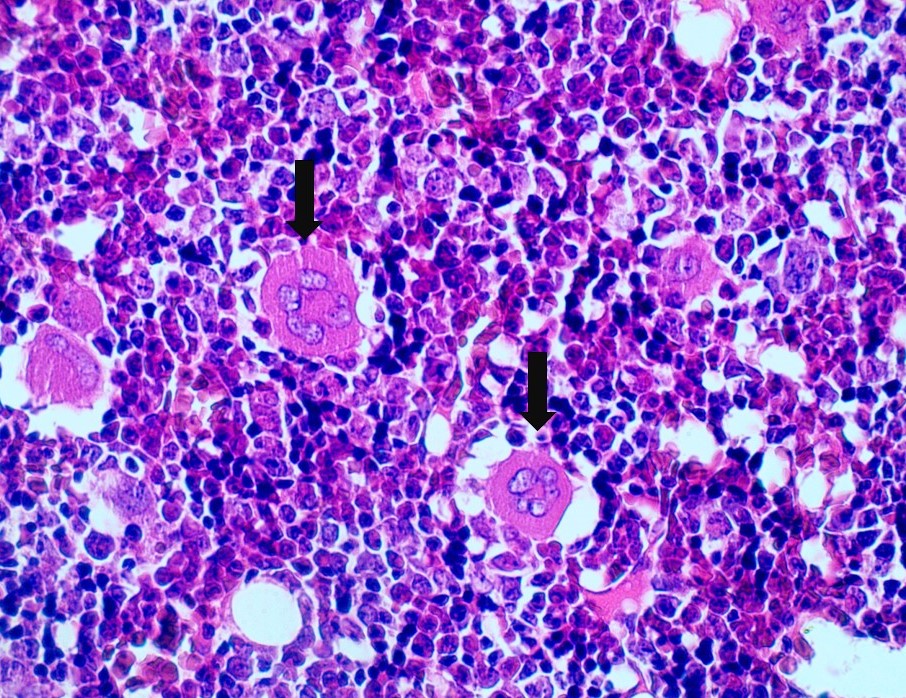

Lamina de osso descalcificado: ossificação endocondral. Aumento de 40x.

Em 1 observa-se uma trabécula óssea. Circulado na periferia da trabécula podemos ver osteoblastos. Circulados no interior das trabéculas observa-se os osteócitos. A seta laranja aponta um megacariócito.

Lamina de osso descalcificado: ossificação endocondral. Aumento de 40x. As estruturas apontadas pelas setas são os megacariócitos encontrados na medula óssea vermelha.